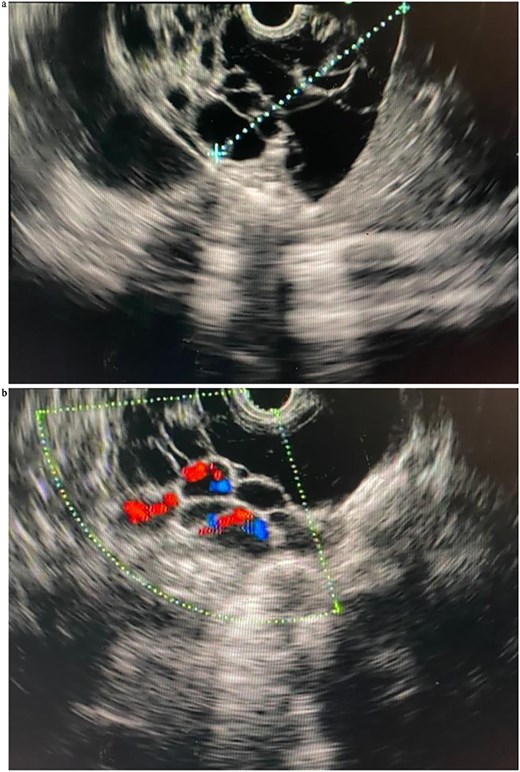

Endoscopic ultrasound (EUS) at our center revealed a large, multiseptated cystic lesion posterior to a structurally normal pancreas (Fig. 2a and b). Aspiration yielded 6 ml of yellowish serous fluid. Biochemical analysis showed low carcinoembryonic antigen (CEA 2.39 ng/ml) and elevated amylase (443 U/l); cytology revealed scattered cyst macrophages and lymphocytes only consistent with pancreatic lymphangioma.

(a) Linear EUS (Olympus ME 1) views of the pancreatic lymphangioma, seen as cystic lesions in the pancreatic parenchyma. (b) Linear EUS (Doppler) (Olympus ME 1) views of the pancreatic lymphangioma, seen as cystic lesions in the pancreatic parenchyma.

EUS was subsequently performed and proved valuable for further characterization. EUS identified a multiloculated, avascular cystic lesion with thin septations—features that are highly suggestive, though not pathognomonic, of pancreatic lymphangioma. A key advantage of EUS lies in its ability to facilitate fine-needle aspiration (FNA) for biochemical and cytological analysis. Fluid from pancreatic lymphangiomas is typically straw colored and known to demonstrate normal CEA levels, high amylase levels, and elevated levels of lactate dehydrogenase and triglycerides [1, 4]. Our sample showed normal CEA levels and high amylase levels and the aspirated fluid was dark yellow and slightly turbid. Cytological analysis revealed a white blood cell population in a benign inflammatory smear, with no atypia. These findings, in combination with the clinical and radiological context, supported the diagnosis of pancreatic lymphangioma.